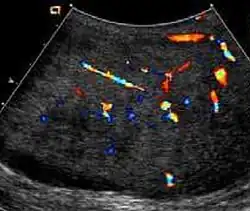

Fibrous pseudotumors, also known as fibromas are thought to be reactive, nonneoplastic lesions. They can occur at any age, about 50% of fibromas are associated with hydrocele, and 30% are associated with a history of trauma or inflammation (Akbar et al., 2003). Although the exact cause of this tumor is not completely understood, it is generally believed that these lesions represent a benign reactive proliferation of inflammatory and fibrous tissue, in response to chronic irritation. Sonographic evaluation generally shows one or more solid nodules arising from the tunica vaginalis, epididymis, spermatic cord and tunica albuginea [Fig. 18]. A hydrocele is frequently present too. The nodules may appear hypoechoic or hyperechoic, depending on the amount of collagen or fibroblast present. Acoustic shadowing may occur in the absence of calcification due to the dense collagen component of this tumor. With color Doppler sonography, a small to moderate amount of vascularity may be seen [Fig. 19].

-

Fig. 18. Fibrous pseudotumor. A homogeneous hypoechoic nodular lesion is seen attached to the tunica associated with minimal amount of hydrocele. -

Fig. 19. Fibrous pseudotumor. With color Doppler, a little vascular flow is seen in this fibrous pseudotumor.